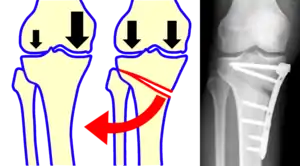

القطع العظمي في الركبة

- الصورة اليمنى تبين مكان قص العظم.

- الصورة اليسرى تبين ساق طبيعية بعد عملية القص.

عادة ما يجرى القطع العظمي في منطقة الركبة بهدف إعادة ارتصاف مفصل الركبة في حالة تآكل المفصل على أحد جانبيه فقط، وذلك بهدف تحويل وزن الجسم عن الجانب المتآكل إلي الجانب السليم. يقوم الجراح بإزالة جزء وتدي الشكل من قصبة الساق أسفل الجانب السليم من الركبة، وهو ما يسمح لعظمتي القصبة والفخذ بالانحناء بعيداً عن الجزء الغضروفي المصاب.

وهذا يشبه مفصلة الباب، فعند اغلاق الباب تلتصق دفّتي المفصل مع بعضهما عند حافة الجدار. وعند فتح الباب، فإن جانب واحد من الباب يظل يضغط ضد حافة الجدار بينما يتحرك الجانب الآخر مبتعداً عنه. وبالمثل، عند إزالة مجرد جزء صغير من العظام، يمكن للركبة أن تنفتح بحيث تضغط على الأنسجة السليمة بينما تزداد المسافة بين عظم الفخذ وقصبة الساق على الجانب التالف فلا تحتك الأسطح الملتهبة للمفصل ضد بعضها البعض.

قد يُستخدم القطع العظمي كبديل لاستبدال كامل الركبة في حالة المرضى صغار السن والمرضى النشطين. فالركبة الاصطناعية قد تتآكل مع مرور الزمن ومع تعرضها للأحمال، وبالتالي فالقطع العظمي هو بديل مناسب يُمَكِّن المريض صغير السن وافر النشاط من الاستمرار في استخدام الجانب السليم من ركبته. وبذلك قد تؤدي عملية القطع العظمي في الركبة إلى تأجيل الاحتياج إلى استبدال كامل مفصل الركبة لما قد يصل إلى 10 سنوات.

إن اختيار المكان المُراد إزالة جزء من العظام منه (على شكل وتدي) يعتمد على مكان الجزء التالف من غضروف الركبة ، والذي تلف بسبب التهاب المفاصل العظمي. النوع الأكثر شيوعا من قطع العظم بسبب التهاب المفاصل العظمي هو قطع أعلى عظم الظنبوب (قصبة الساق)، وهذا النوع يتعامل مع أضرار الغضروف التالف الواقع في الجزء الداخلي (الوسطي، الإنسي) من الركبة، ويستغرق إجراء هذه الجراحة عادة ما بين 60-90 دقيقة لأدائها.

خلال عملية قطع أعلى عظم الظنبوب (قصبة الساق)، يقوم الجراحون بإزالة جزء إسفيني من العظام (على شكل وتد) من الجزء الخارجي من الركبة، وهو ما يجعل الساق تنحني قليلا إلى الداخل. هذا يشبه إعادة تنظيم ركبة شخص متقوس القدمين للداخل لتصبح ركبة روحاء تميل إلى الخارج. بعد العملية، ينتقل وزن المريض إلى الجزء الخارجي (الوحشي) من الركبة حيث يكون الغضروف لا يزال بحالة جيدة وليس تالفاً.